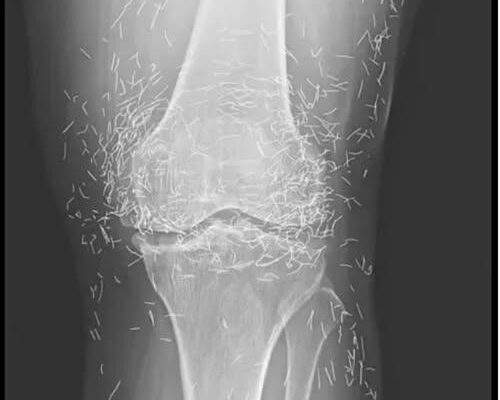

When a 65-year-old woman went in for an X-ray to uncover the cause of her unrelenting knee pain, doctors expected to see signs of arthritis. What they found instead left them stunned: hundreds of tiny gold acupuncture needles embedded deep inside her tissue — a hidden legacy from years of alternative treatment.

When radiologists reviewed the woman’s X-ray, they couldn’t believe their eyes. Her knees were peppered with countless specks of metallic glimmer — hundreds of gold acupuncture needles, permanently lodged under her skin.

Unlike typical acupuncture sessions, where thin needles are temporarily inserted and then removed after a short time, this particular technique left the needles in place indefinitely. The needles, believed to be made of sterile gold, were meant to provide “ongoing stimulation” to relieve pain and improve joint function.

This type of gold thread acupuncture is still practiced in some Asian countries as a treatment for osteoarthritis and other joint conditions, particularly in older patients who may not tolerate medications well. The idea behind it is simple but controversial: implant gold threads around painful joints to continuously stimulate healing energy.

What’s more, the presence of those gold needles complicates future imaging tests, which are vital for diagnosing many age-related health conditions. X-rays can become difficult to interpret, and MRIs — a common and essential diagnostic tool — are often off-limits for patients with metal objects inside them.

“Needles left in the body may move during an MRI and potentially damage tissue or even rupture a nearby artery,” Guermazi warned.